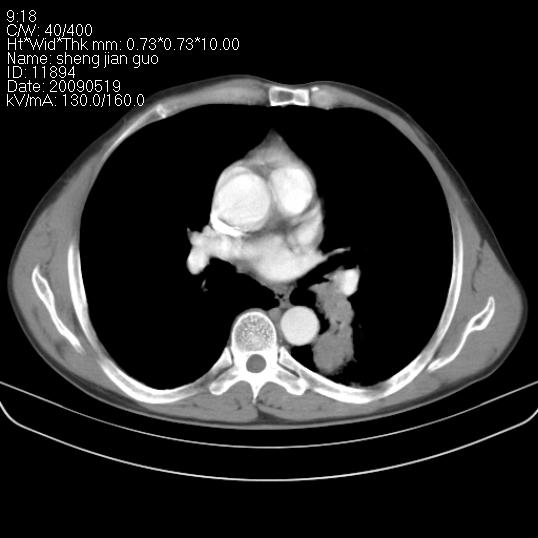

以下是引用zjzjr在2009-5-19 17:25:00的发言:[br]支持楼主考虑,另左肺下叶阻塞性炎症。

以下是引用zhao_bin2008在2009-5-19 17:48:00的发言:[br]支持左肺下叶周围型肺癌并阻塞性肺炎。

以下是引用zsl6918在2009-5-20 7:10:00的发言:[br]左侧中心型肺癌!